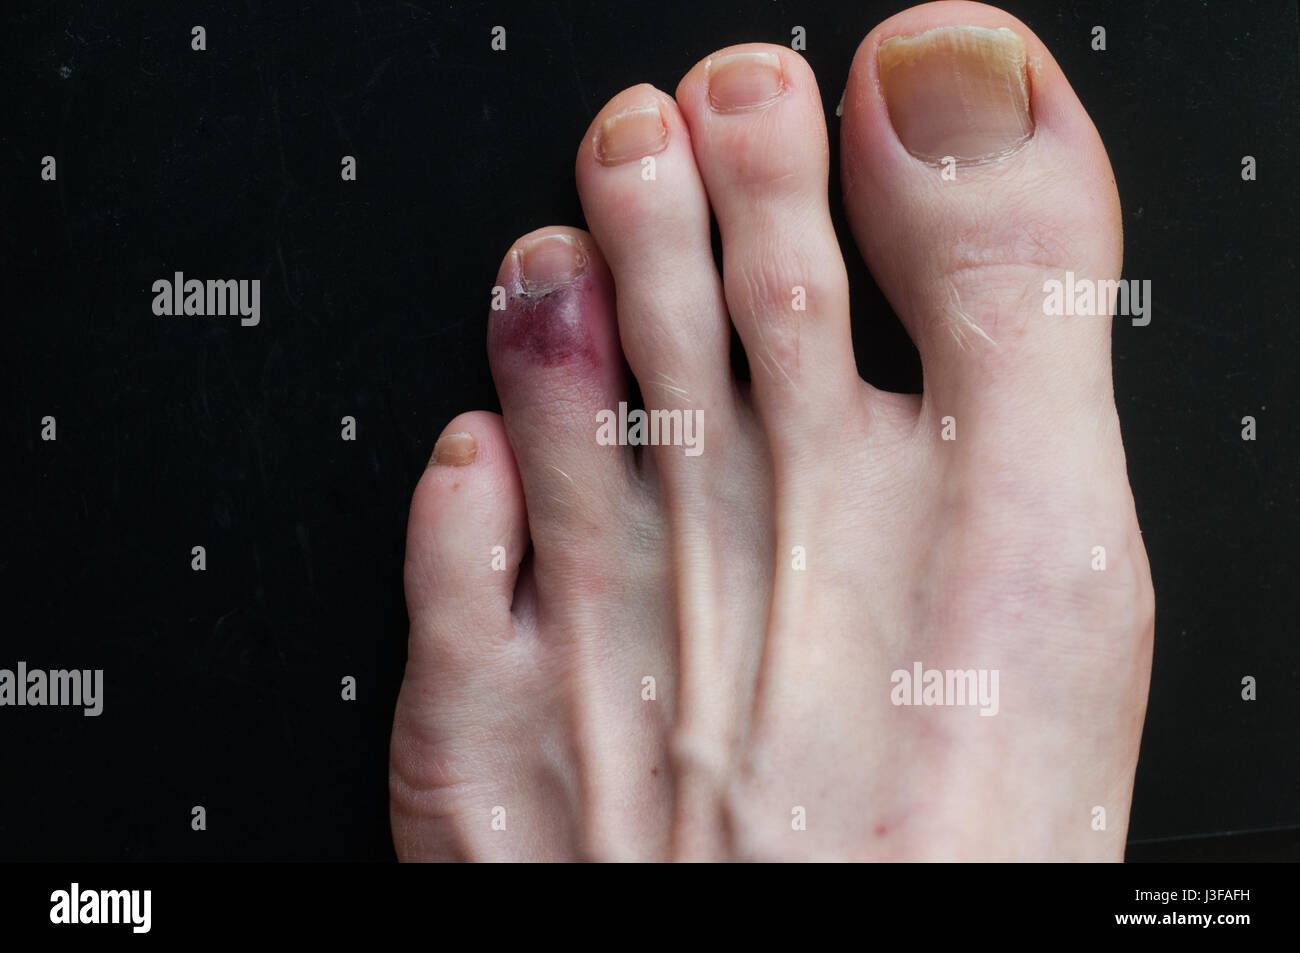

RF2FM8YC2–Blutergüsse an der kleinen Fußspitze. Nahaufnahme der gebrochenen kleinen Zehe eines älteren Mannes, der Verfärbungen zeigt.